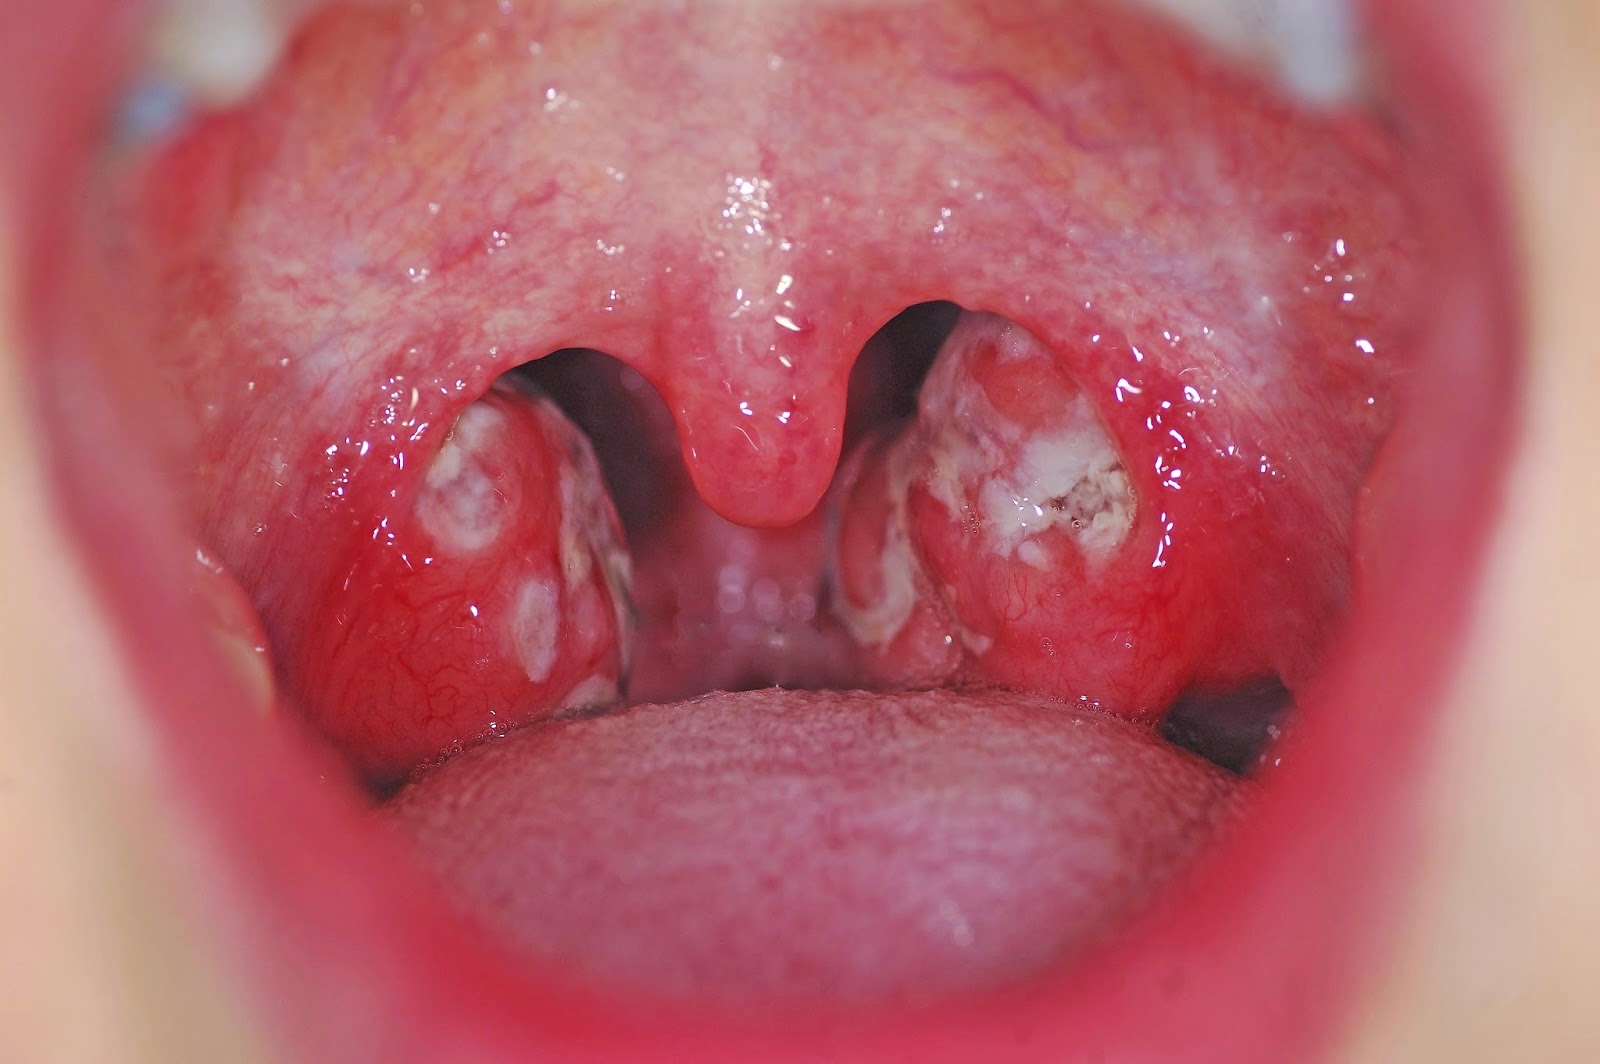

Faringitis: causas, síntomas y tratamiento 😈

Faringitis: qué es, síntomas, causas, tratamiento y remedios 😈